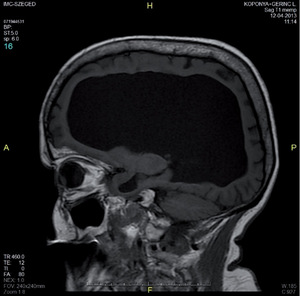

3.6.1. Hydrocephalus (59–63. ábra)

- Koponya-MRI: kamrák mérete– a fentiek, valamint occlusiót okozó eltérés kimutatása,sagittalis képeken a III. kamra fenekének lenyomottsága,aqueductus stenosis kimutatása.